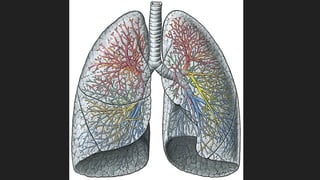

ARBORIZACIÓN BRONQUIAL

Cuando penetran los bronquios principales al pulmón se dividen sucesivamente como las ramas

de un árbol.

Bronquios Secundarios o Lobares

Bronquios Terciarios o Segmentarios

Bronquiolos carecen de cartílagos y de glándulas.